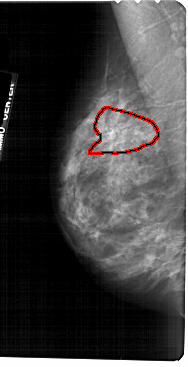

A_1724_1.LEFT_CC

FILE: A_1724_1.LEFT_CC.OVERLAY

TOTAL_ABNORMALITIES 1

ABNORMALITY 1

LESION_TYPE CALCIFICATION TYPE PLEOMORPHIC-FINE_LINEAR_BRANCHING DISTRIBUTION SEGMENTAL

ASSESSMENT 4

SUBTLETY 3

PATHOLOGY MALIGNANT

TOTAL_OUTLINES 1

BOUNDARY